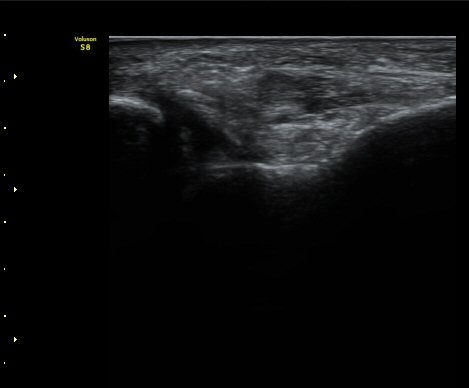

ÃÊÀ½ÆÄ°Ë»çÇÏ Àü°Å°ñºñ°ñÀÎ´ë ºÎÇϰ˻翡¼­ °Å°ñ°ú ºñ°ñ°£ ºÒ¾ÈÁ¤ÀÌ °üÂûµÈ´Ù(÷ºÎ µ¿¿µ»ó).

Á¤Áö »óÅÂÀÇ Àü°Å°ñºñ°ñÀδë ÃÊÀ½ÆÄ°Ë»ç¿¡¼­´Â ÀδëÀÇ Àú¿¡ÄÚ ºÎÁ¾ÀÌ °üÂûµÇ´Âµ¥

ÀÌ ¼Ò°ßÀ¸·Î´Â ÀÌ ÀδëÀÇ ±â´É ¼Ò½ÇÀ» È®ÀÎÇÒ ¼ö ¾ø´Ù.

±×·¯³ª ÃÊÀ½ÆÄ Åõ½ÃÇÏ ºÎÇϰ˻縦 ½ÃÇàÇÏ¸é °Å°ñ°ú ºñ°ñ»çÀÌÀÇ ¾ÈÁ¤¼ºÀÌ ÈѼյǾî

º¸´Ù Àû±ØÀûÀÎ Ä¡·á°¡ ÇÊ¿äÇÑ °ÍÀ¸·Î ÆÇ´ÜµÈ´Ù.